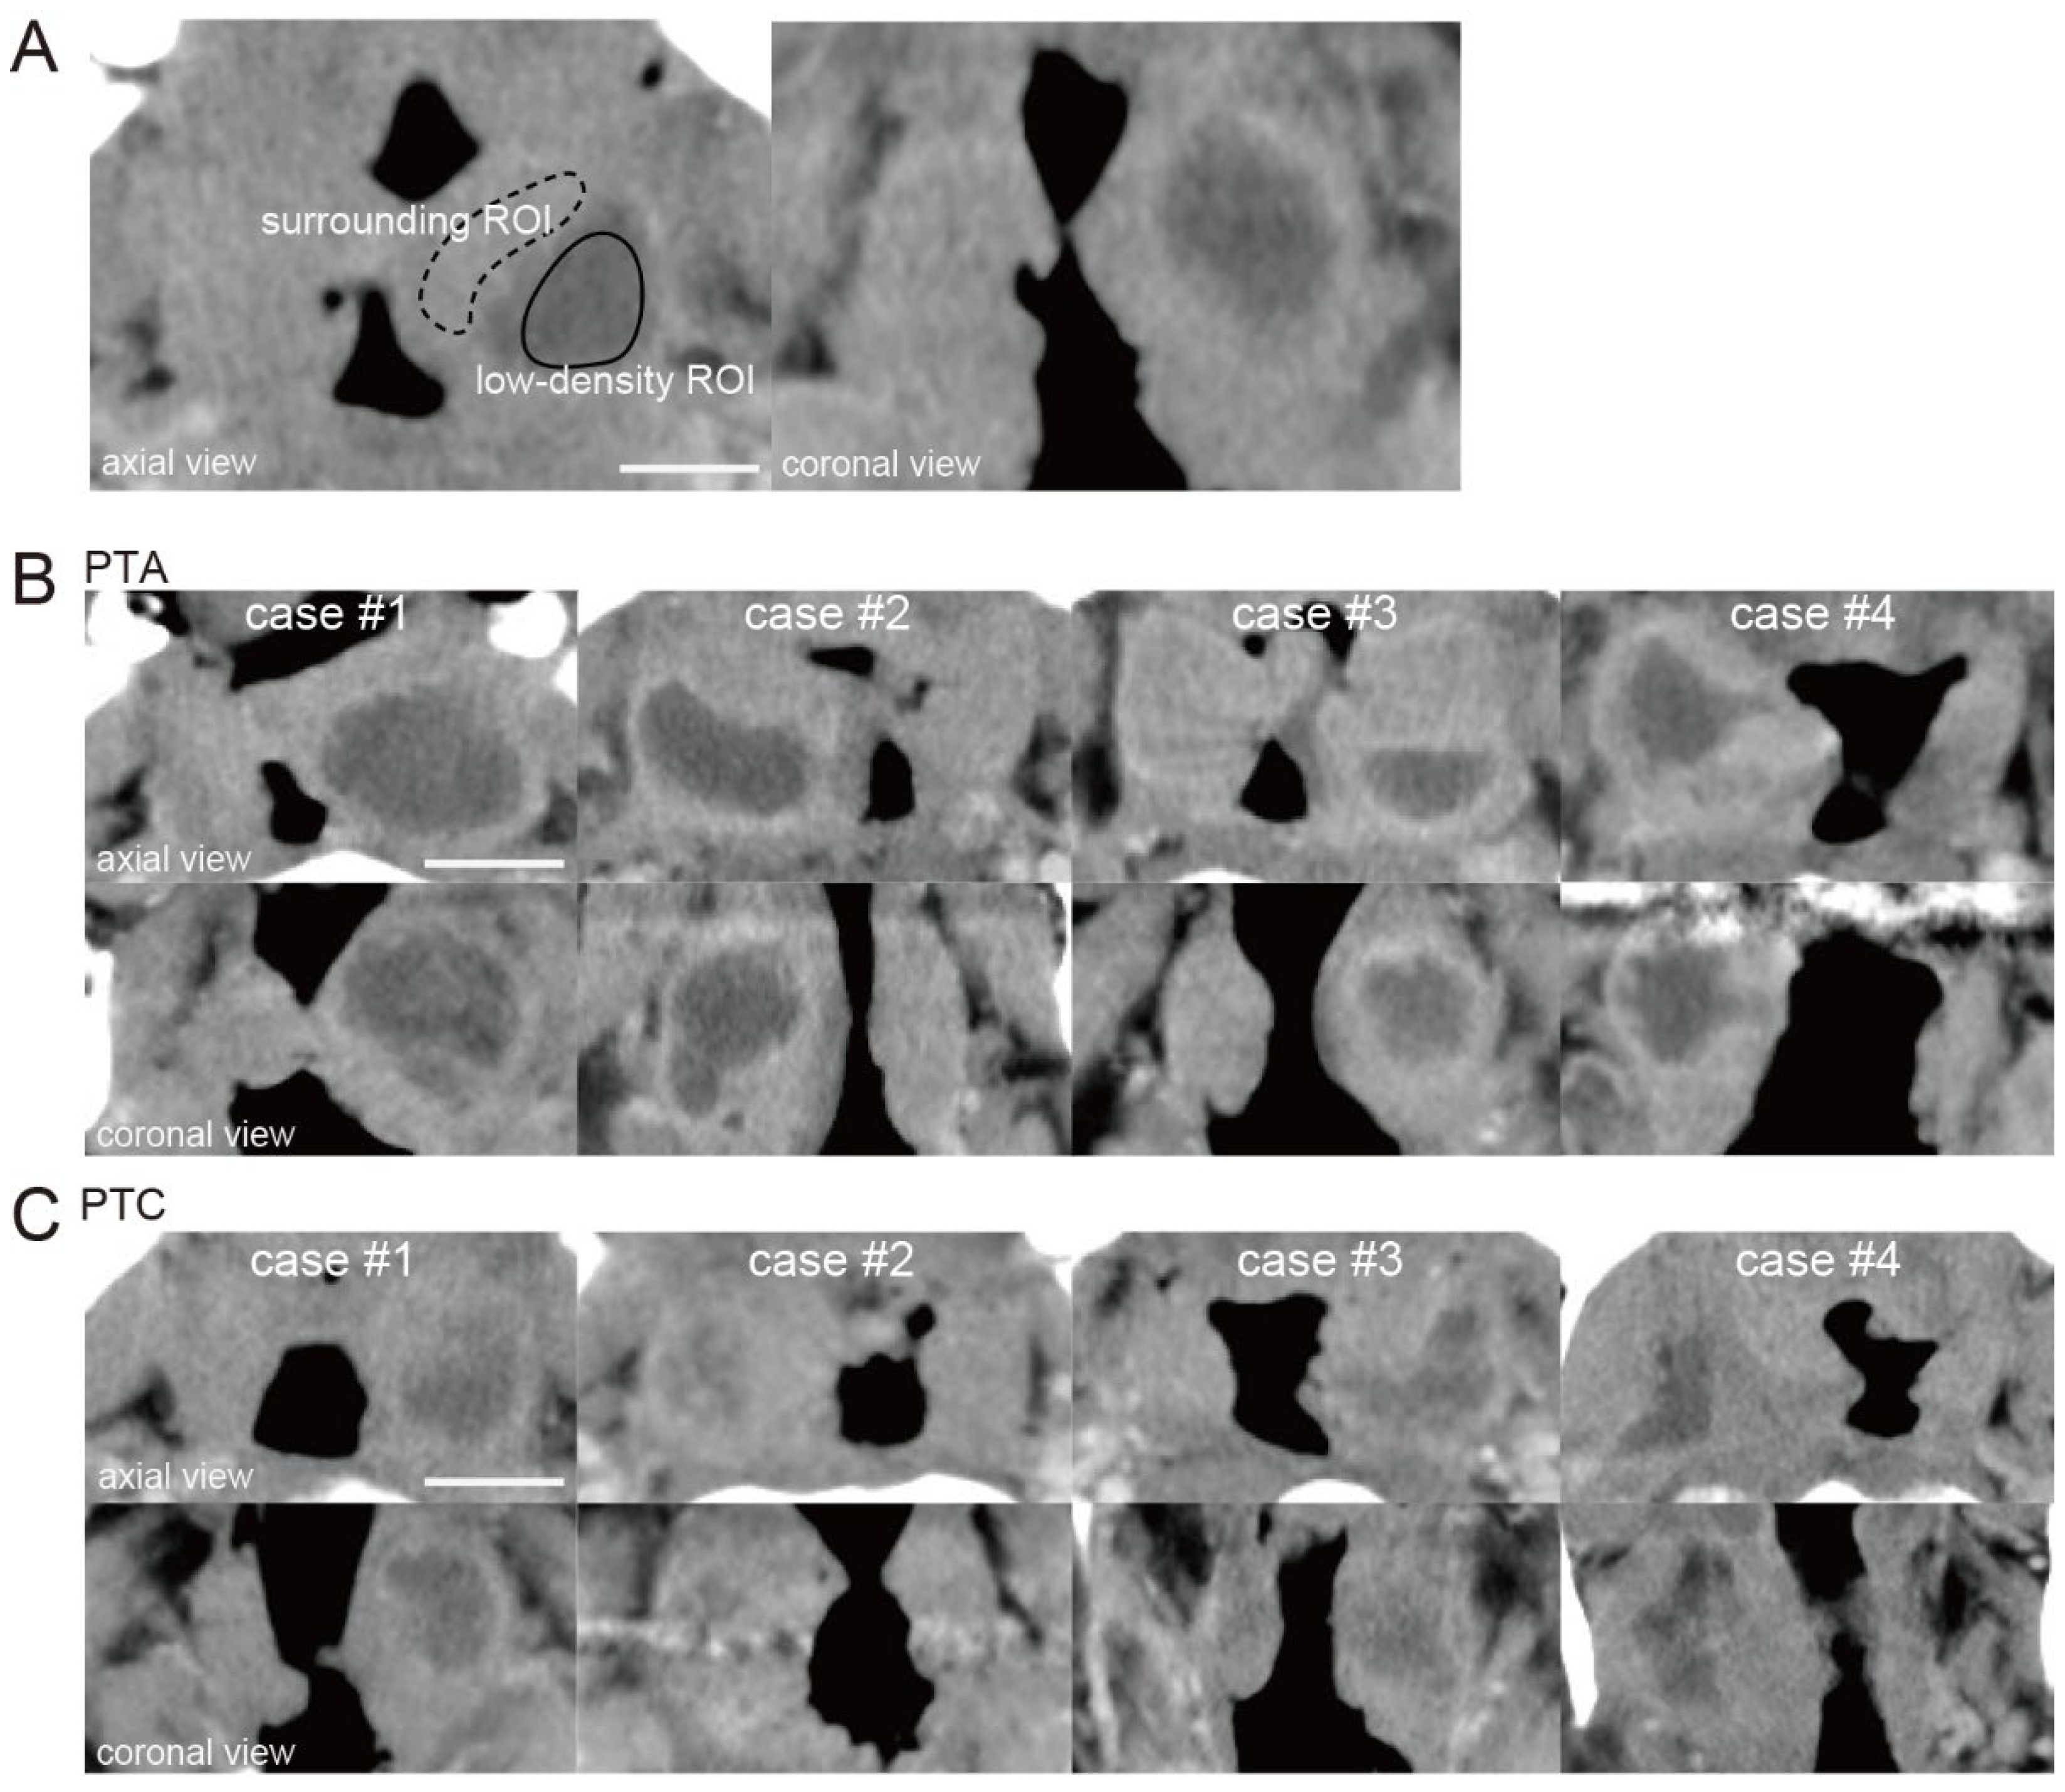

The ROI for the low-density area (low-density ROI) was surrounded by a solid line, and the ROI for the surrounding area (surrounding ROI) was surrounded by a dotted line (Figure 1A). The relative CT number in the low-density area was calculated by dividing the CT number of a low-density area by that of an area surrounding the low-density area.

Figure 1B shows four representative PTA cases in which pus had been drained by puncture or incision. Figure 1C shows four representative PTC cases in which pus had not been drained. When the relative CT numbers of the low-density areas were measured in PTA and PTC cases, a slight difference was observed between the two (relative CT number; PTAs: case #1; 0.61, case #2; 0.64, case #3; 0.55, case #4; 0.57, PTCs: case #1; 0.39, case #2; 0.24, case #3; 0.35, case #4; 0.42).

Figure 1. CT images of cases of peritonsillar abscess (PTA) and peritonsillar cellulitis (PTC). (A) ROI setting. The ROI was selected from the low-density area identified on the axial contrast-enhanced CT image (low-density ROI, solid circle). The surrounding area of the low-density area was set as the surrounding ROI (surrounding ROI, dotted circle). ROI, region of interest; scale bar, 20 mm. (B) Representative CT images of PTA cases (case #1 to #4). The upper images show axial sections, and the lower images show coronal sections. Scale bar, 20 mm. (C) Representative CT images of PTC cases (case #1 to #4). Scale bar, 20 mm.